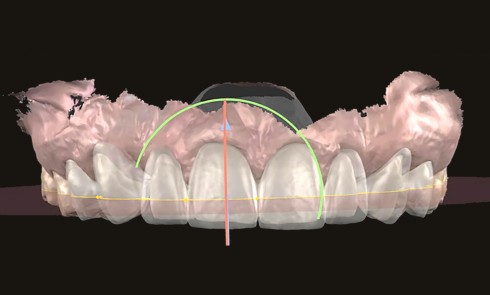

La réhabilitation esthétique et fonctionnelle d’un sourire repose sur une approche raisonnée et progressive, conforme au gradient thérapeutique décrit par...Planification digitale du sourire. Du mock-up de motivation au mock-up fonctionnel

Mock-up de motivation / Données esthétiques Le rôle essentiel du mock-up de motivation Le mock-up de motivation constitue une étape...Réhabilitation esthétique sur substrat dyschromié : quelles sont les stratégies possibles ?